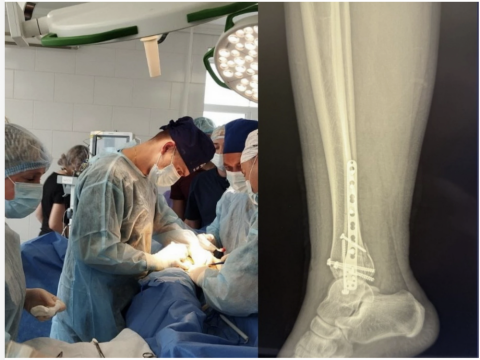

Після зменшення набряку та стабілізації стану пацієнта фахівці лікарні виконали складне оперативне втручання, яке включало:

- відкрите зіставлення уламків правої малогомілкової кістки та остеосинтез пластиною і гвинтами;

- репозицію переломів медіальної кісточки та заднього краю дистального відділу великогомілкової кістки з фіксацією гвинтами;

- фіксацію міжгомілкового синдесмозу гвинтом для відновлення стабільності гомілковостопного суглоба.